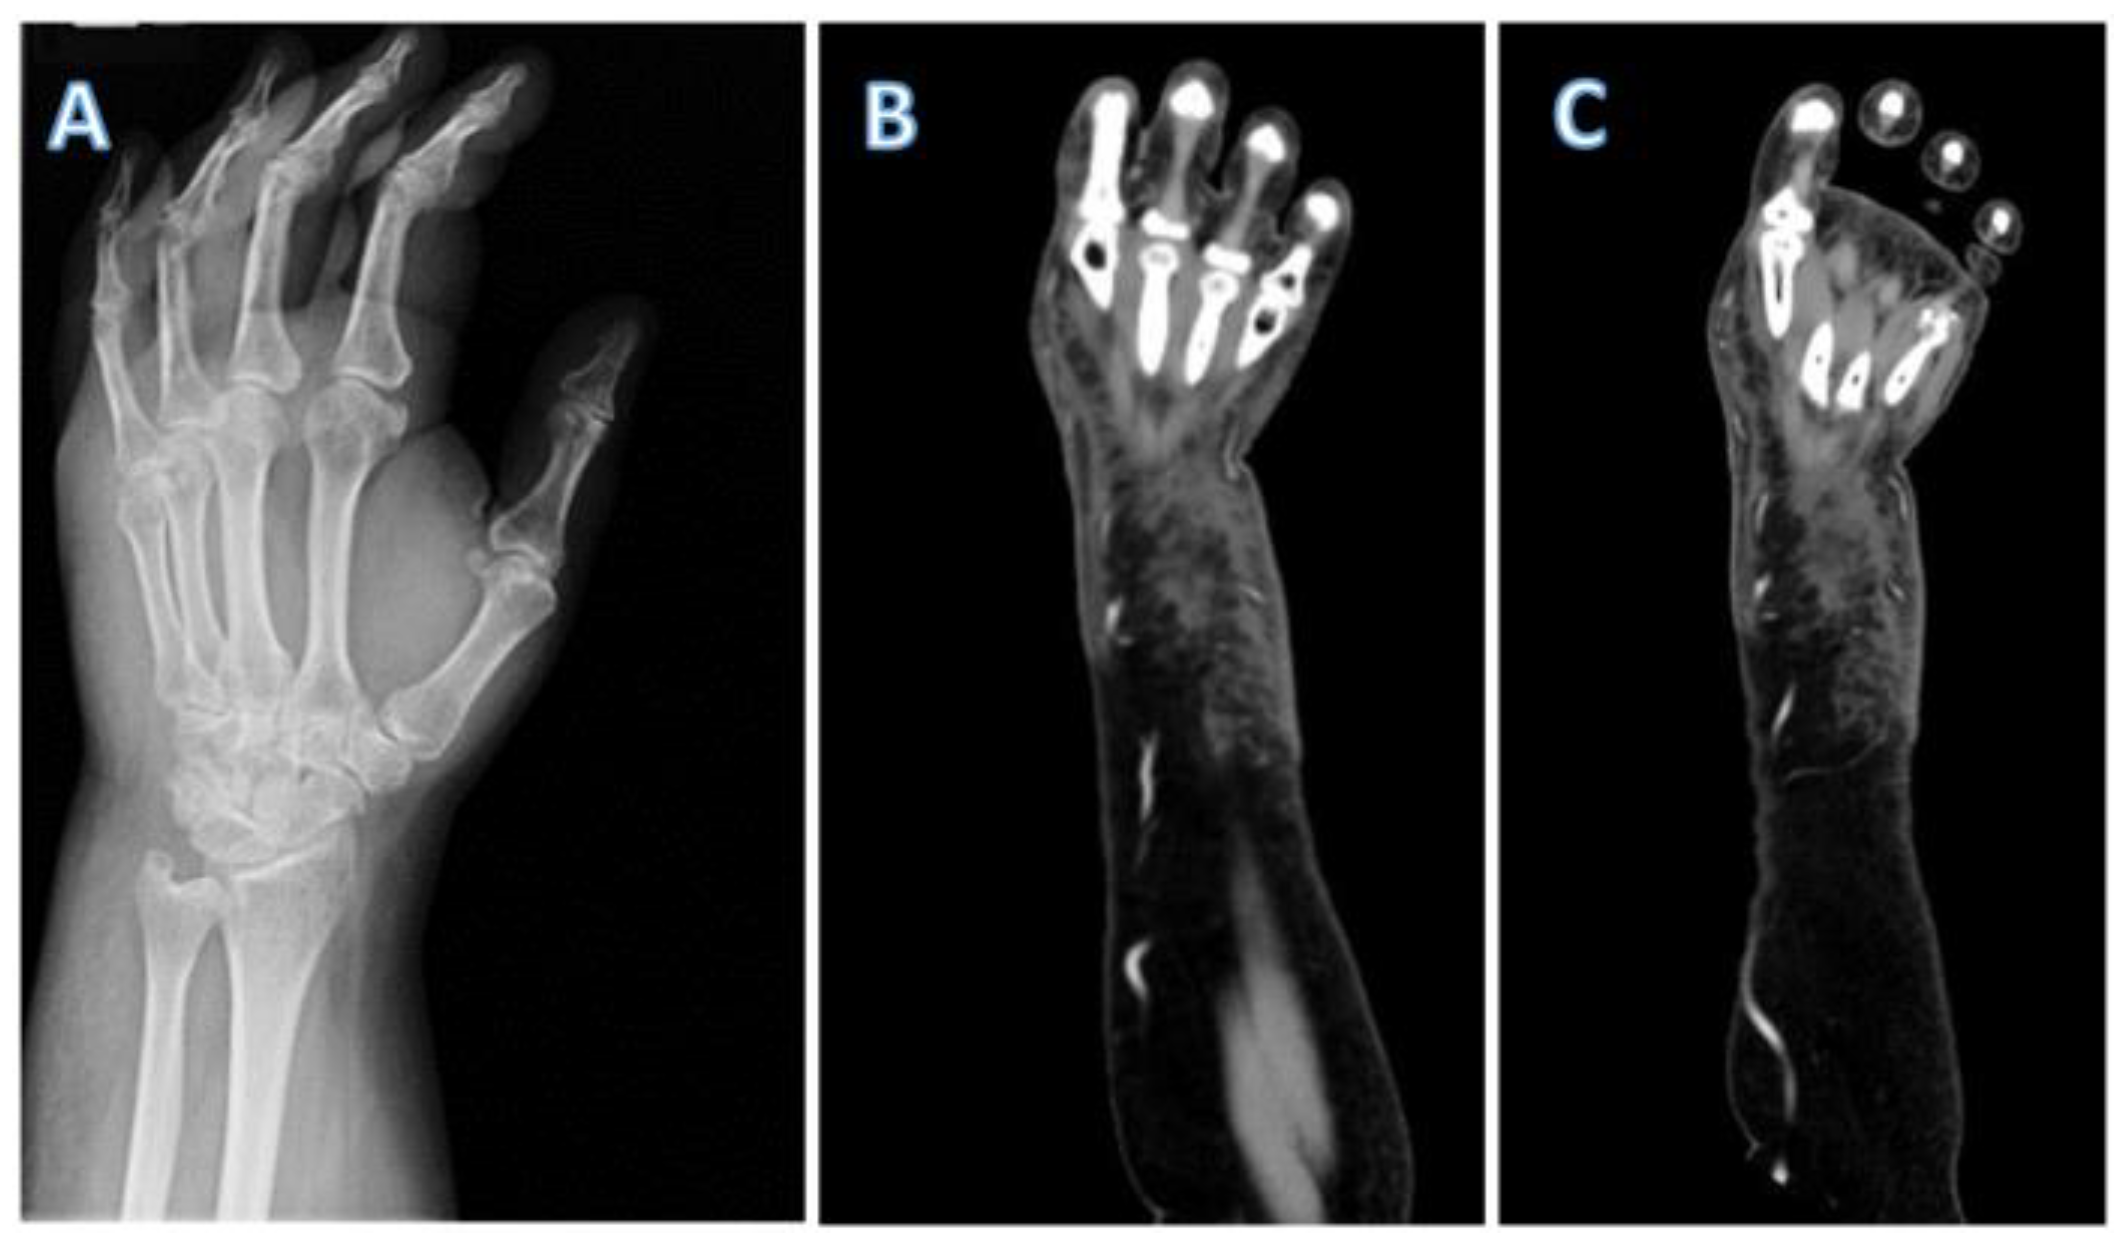

A 61-year-old female presented to an urgent care 24 hours after a canine bite with worsening pain and swelling of her hand. Her past medical history was significant for morbid obesity (BMI 54 kg/m2), bipolar disorder and psoriatic arthritis treated with methotrexate for the past 3 years. At the urgent care she was given oral amoxicillin-clavulanate 875 mg-125 mg twice a day but after 48 hours the swelling and pain intensified prompting her to go to the emergency room where severe swelling, erythema and limited range of motion of her left hand were observed. In the emergency room she was febrile to 38.6 °Celsius, tachycardic to 128 beats per minute and had a leukocytosis of 15,800 cells/µL (89% neutrophils). C-reactive protein was 13.1 mg/dL and erythrocyte sedimentation rate was 104 mm/h. Given the severity, the patient was admitted, and a CT of the left upper extremity showed extensive soft tissue inflammation of the dorsum of the hand, but no abscesses were seen (Figure 1). Intravenous vancomycin 2 grams every 12 hours and ampicillin-sulbactam 3 grams every 6 hours were initiated and an urgent hand surgical consultation was obtained after which surgical intervention was promptly conducted.

Figure 1. (A) X-ray of the left hand showing marked soft tissue swelling. (B,C) Coronal views of a CT scan of the left upper extremity showing marked soft tissue swelling and cellulitis in the dorsal aspect of the hand extending to mid forearm.